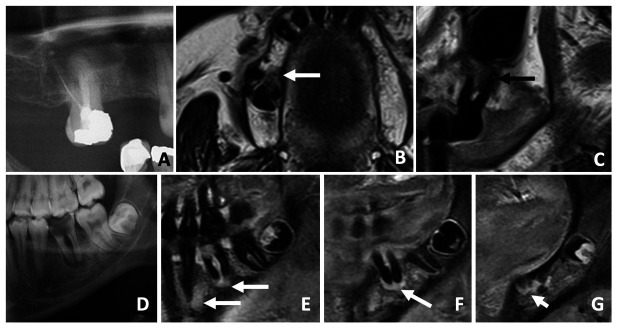

Abstract Image